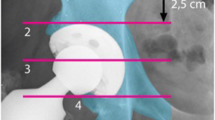

Bone mineral density was measured in four zones defined by Wilkinson et al. [7] and subsequently modified by Laursen et al. [8] (Fig. 1). The change in bone mineral density in each zone was calculated by dividing the bone mineral density value from each examination by the baseline value measured two days postoperatively. The ratio was expressed as a percentage of the baseline value. Each patient's individual regions of interest (ROI) were saved and used for subsequent examinations to reduce measurement errors.